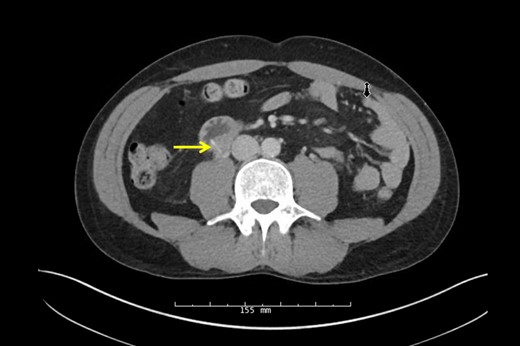

A 38-year-old male presented to the hospital with a chief complaint of abdominal pain and hematuria 1 day after eating a barbecue pulled pork sandwich. He described the pain as ‘deep’ in his abdomen, sharp and non-radiating with no episodes of nausea, emesis or diarrhea. He denied any dysuria or frequency. The patient's past medical and surgical history was unremarkable. He had no abnormalities on his laboratory values besides a urinalysis demonstrating 2+ blood and 11–24 RBCs/hpf. Physical examination revealed point tenderness to deep palpation to the right of his umbilicus, but his abdomen was soft with no signs of peritonitis. An upright abdominal X-ray was unremarkable; however, a CT of his abdomen demonstrated a 2-cm linear density representing the FB in the posterior third portion of the duodenum perforating into the retroperitoneum abutting the right ureter causing hydronephrosis (Figs 1 and 2, arrow). Two separate attempts were made at endoscopic retrieval in the first 24 h without successful visualization or removal of the FB. Due to the ureteral involvement and hydronephrosis, an operative intervention was recommended.

CT scan of linear opaque FB traversing the posterior wall of the duodenum abutting the ureter.